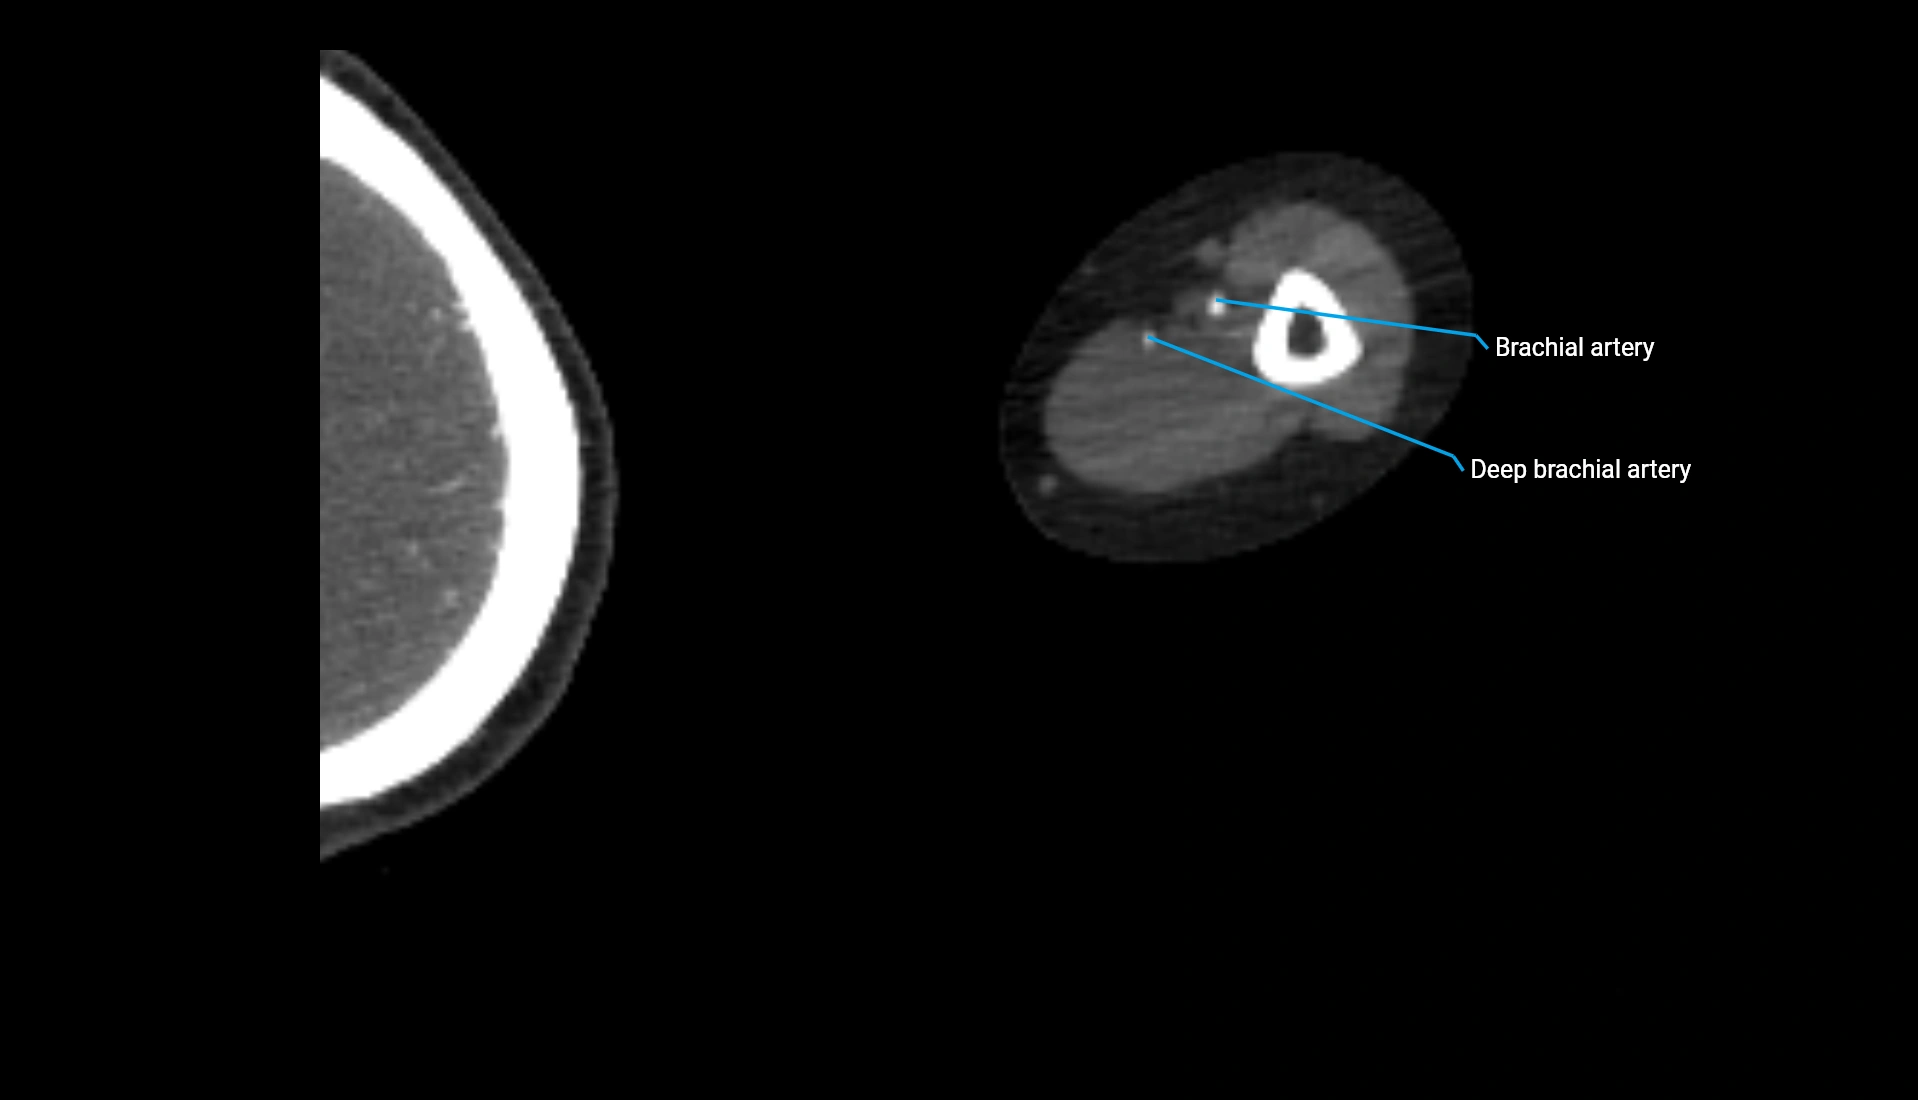

CT Appearance

Non-Contrast CT:

• Cortex: High-density, sharply defined

• Subchondral bone: Dense cancellous matrix

• Articular surface: Smooth concave contour articulating with the capitellum

• Excellent for evaluating bone integrity, alignment, and subtle fractures

Post-Contrast CT:

• Bone: No enhancement

• Joint capsule and synovium: Mild enhancement outlining the joint

• Improves contrast between soft tissues and bony margins

• Useful in detecting subtle joint abnormalities or postoperative changes